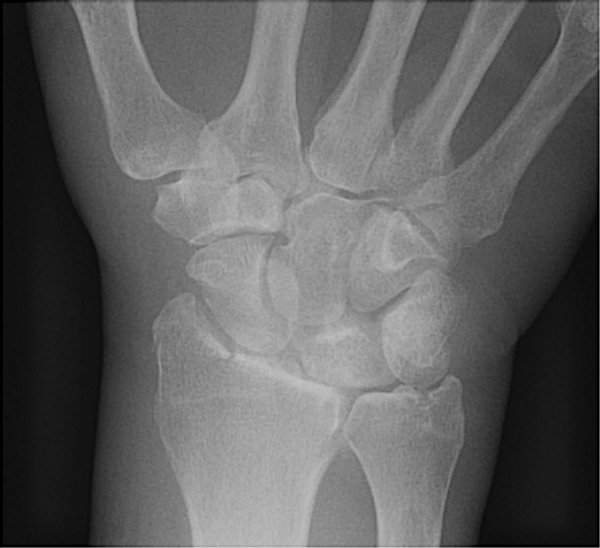

Return to Chauffeur (Backfire)